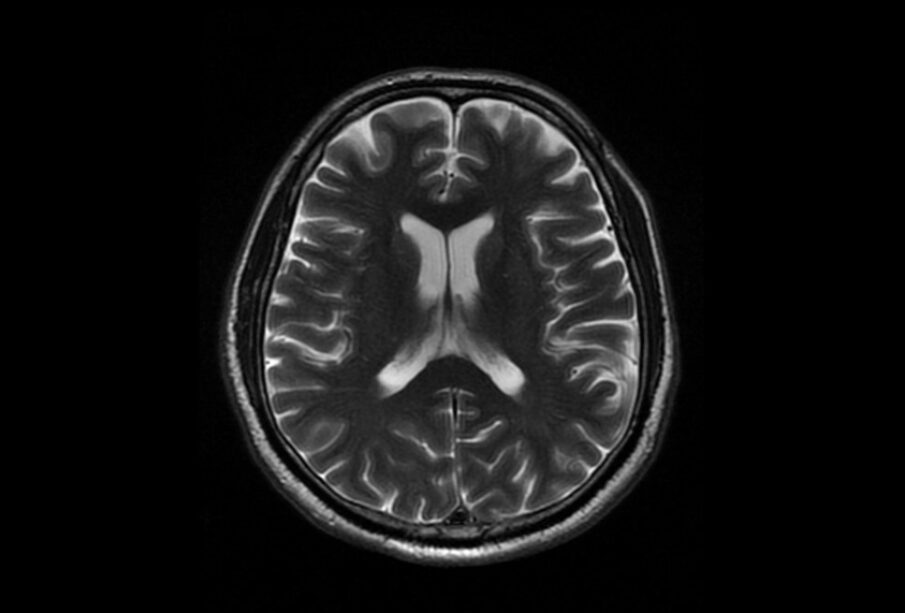

Nustatyti auglio buvimą ir jo ypatybes leidžia įvairūs radiologiniai tyrimai. Dažniausi – galvos magnetinio rezonanso (MRT) arba kompiuterinės tomografijos (KT) tyrimai. Šie metodai leidžia matyti auglio dydį, tikslią vietą ir padeda atskirti skirtingas navikų rūšis.

Siekiant tikslumo, dažnai naudojama kontrastinė medžiaga – ji padeda išryškinti navikus bei jų kraštus. Specializuoti tyrimai, tokie kaip funkcinis MRT ar pozitronų emisijos tomografija (PET), kartais taikomi planuojant operacijas ar tiriant sudėtingus atvejus.

Kiekvienam naviko tipui būdinga savita išvaizda vaizdinimo tyrimuose. Kai kurie augliai (pvz., oligodendrogliomos) gali sukelti kalcio sankaupas, kurios aiškiai matomos KT nuotraukose. Glioblastomos dažnai plinta į keletą galvos sričių, o metastazės linkusios formuotis šalia smulkių kraujagyslių.